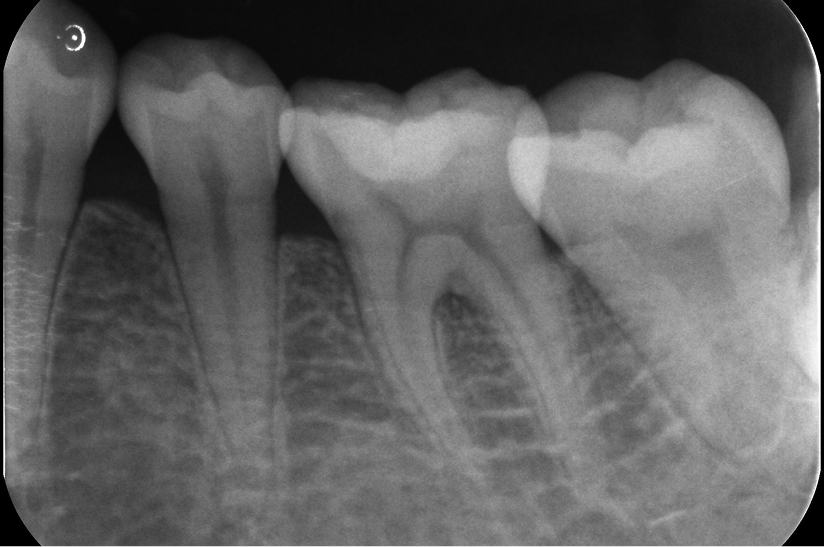

大臼歯の再根管治療を行った症例

タップで写真の拡大ができます。

Before&After(根管治療)

Before

Before&After(根管充填)

主訴

歯茎が腫れて、噛むと違和感がある

治療内容

再根管治療(大臼歯)

治療期間

1ヶ月

治療費用

165,000

治療の

リスク

処置中に歯肉縁下におよぶ重度のう蝕や破折を認めた場合、治療を中断する可能性があります。術後も症状が残る場合は追加の処置が必要になる可能性があります。